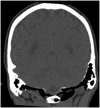

Hyperpneumatization is a rare pathological process where air-filled cavitation form within solid bone architecture occurring at sites where physiological pneumatization is not seen. Extension of this process into the atlanto-occipital region is considered extremely rare and is only quoted several times in the literature. In this case report, we present a 66-year-old man who presented with an 8-month history of a worsening frontal headache and blocked sensation in his left ear. Subsequent CT head evaluation revealed hyperpneumatization affecting C1 vertebra, temporal and occipital bones with extension into the clivus. A rare complication of epidural emphysema was seen. The aetiology of hyperpneumatization is uncertain, although it is thought to be either congenital or acquired. In our case, clinical suggestion of eustachian tube dysfunction and radiological findings of thickened sinus mucosa and a unilateral nasal polyp point to chronic recurrent coryzal illnesses, which may indicate an acquired mechanism. Management is mostly conservative with surgical management reserved for high risk or refractory cases.